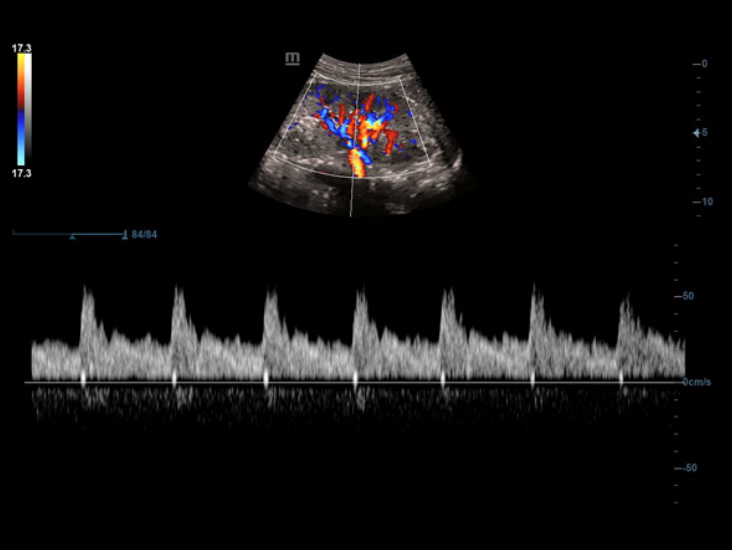

Smart Track

Smart Track? ?? ??? ????? ?? ??? ???? ???? ???? ? ????. ?? ??? ?? ??, ??, PW ????? ????? ??? ?? ???? ??? ???? ? ????. ??? ?? ?? ?????? ??? ?? ??? ?? ??????.